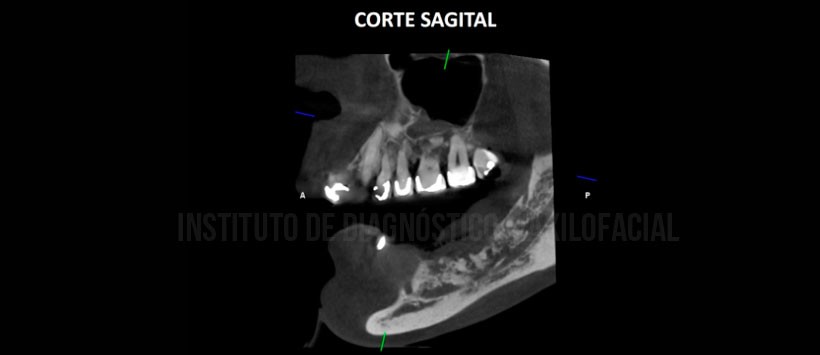

A la evaluación de la tomografía volumétrica (CBCT) cortes axiales (Figura 2), coronales (Figura 3),sagitales (Figura 4), transaxiales (Figura 5) y tangenciales (figura 6) se aprecia alteración en el patrón óseo trabecular localizado en el cuerpo mandibular izquierdo caracterizado por ocasionar alteración de la continuidad de la cima del reborde alveolar, múltiples lesiones osteolíticas de límites difusos, comprometen las corticales del conducto dentario inferior y ocasionan erosión a nivel de la tabla ósea lingual, con evidencia de áreas con incremento de densidad y presencia de secuestros óseos.